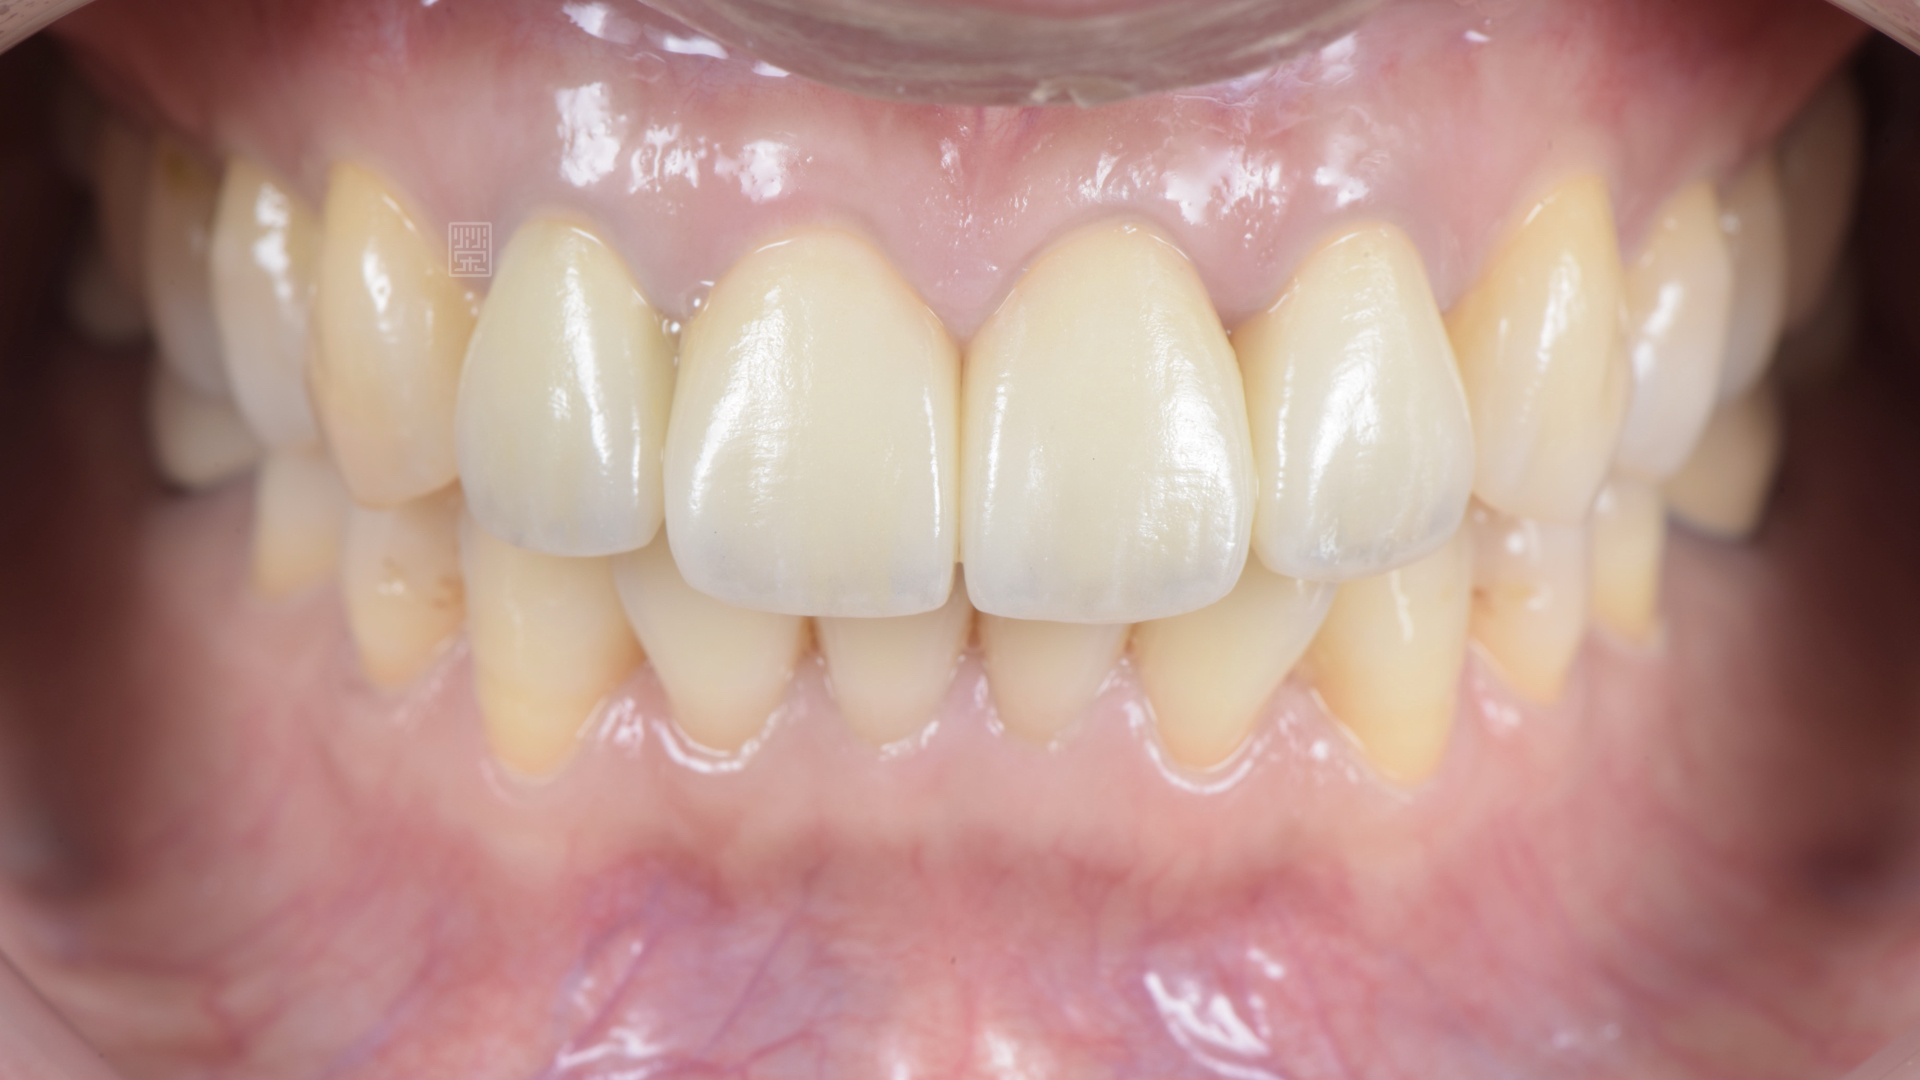

門牙全瓷冠完成

和諧燦爛的笑容